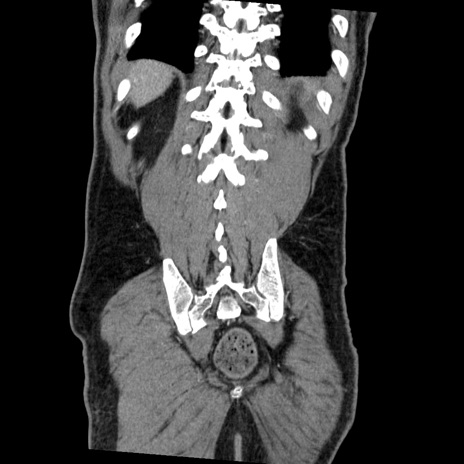

症例22(冠状断像)

【症例】50歳代男性

【主訴】腹痛

【現病歴】AVMからの被殻出血のため回復期リハ病棟入院中。 本日午後3時頃急に下腹部痛が出現した。

【既往歴】AVM、被殻出血、虫垂炎、高血圧

【身体所見】意識晴明、左半身不全麻痺、会話の理解は良好、36.5°C、腹部:膨隆、全体に板状硬、下腹部正中に圧痛点あり、反跳痛-、筋性防御不明、右下腹部にope scar

【データ】WBC 9400、CRP 0.06